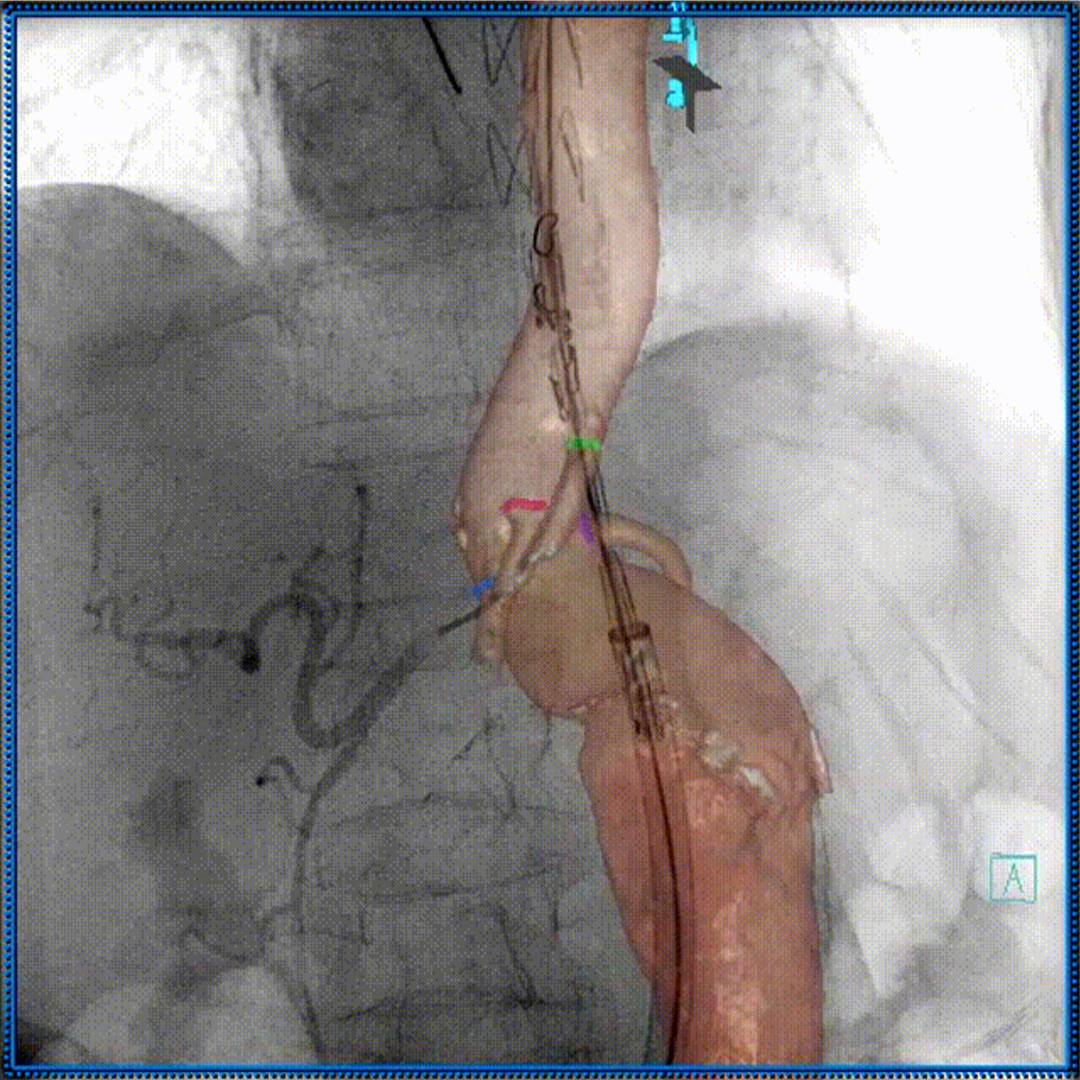

病例2:f-TEVAR(双3D技术,体外三开窗重建弓部三分支)

3D影像融合

3D打印

术中3D影像引导,主体支架精准定位

3D影像引导下,

主体支架窗口与弓上三分支开口对位

依次超选无名、左颈总及左锁骨下动脉

术后造影,支架形态良好,分支血流通畅